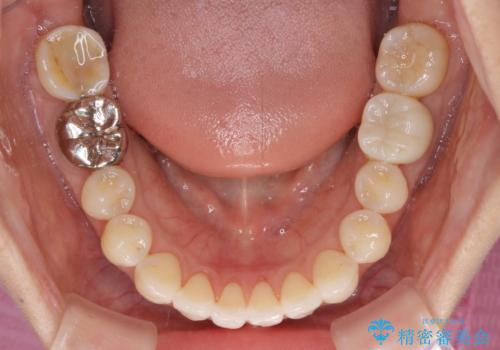

左下大臼歯は根管治療が必要であったため、矯正治療前に根管治療を行い、その後矯正治療を行うこととしました。

矯正治療後には期にある銀歯を全てセラミッククラウンなどで補綴治療することとしました。

インビザライン・ライトによる矯正治療であったので、時間をかけずに治療を終えることができました。

口を開ける度に目立っていた銀歯もセラミックで自然な口元の印象となりました。